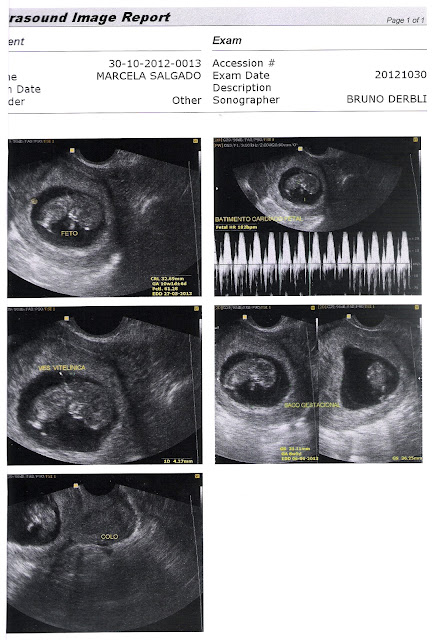

A minha primeira ultra fiz com 10 semanas, e é só para ver como está o feto, ele parece um grão de feijão e ainda não esta na placenta e nem se alimenta pelo cordão umbilical, nesta fase ele ainda está no saco gestacional e se alimenta pela Ves. Vitelínica, ele está com quase 3cm. Foi a primeira, então foi inesquecível.

Esta semana fiz uma nova ultra, no período de 11 a 13 semanas, é importante fazer uma ultra clamada, TRANSLUCÊNCIA NUCAL, este exame é para detectar a probabilidade de ter um filho com alguma anomalia cromossômica, como a síndrome de down, e na terça-feira fiz este exame e a TN do meu bebê deu muito pequena, diminuindo este risco, quando a TN é alta, o risco é maior, TN é um líquido que fica atrás do pescoço do bebê, e conforme o bebê vai crescendo não dá mais para visualizar, por isso só pode ser feita neste período.

Durante este exame, a doutora ficou assim apavorada com o meu Bebê, gente ele não parava, ele estava de ponta a cabeça, depois ficou de bruços, e depois ficou de ladinho, é uma espoleta este meu bebê, ela teve que empurrar muito a minha barriga para ele deitar para ela poder conseguir finalizar o exame, mas mesmo assim, vocês vão ver que nesta foto da ultra as fotos estão meio fora de foco poque ele não parava, srsrrsrsrrsrs... E o bebê, em menos de duas semanas quase dobrou de tamanho está com quase 6cm, como cresce rápido, é muito mágico, Deus é muito perfeito.